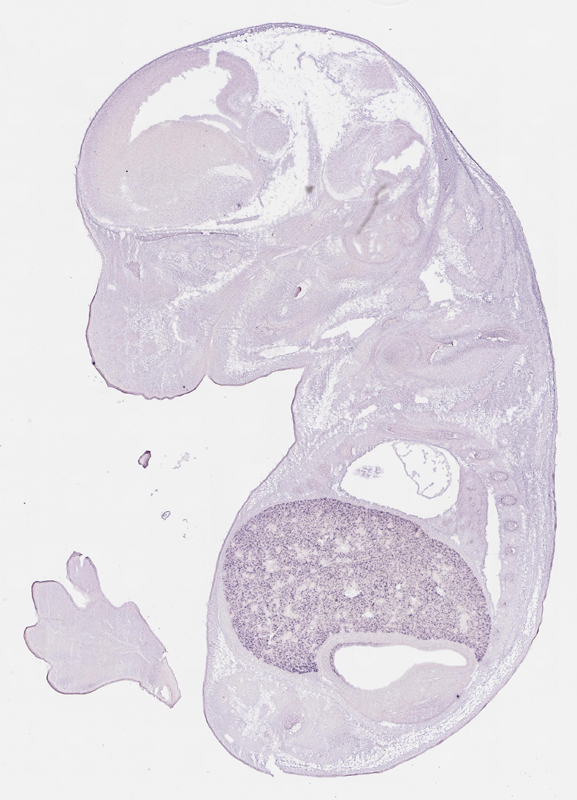

Reference: J:153498 Diez-Roux G, et al., A high-resolution anatomical atlas of the transcriptome in the mouse embryo. PLoS Biol. 2011;9(1):e1000582

Gene symbol: Cyp2d10

Gene name: cytochrome P450, family 2, subfamily d, polypeptide 10

Specimen euxassay_000877_01: embryonic day 14.5 (more )

TS23: liver lobe Strong Uniform euxassay_000877_01